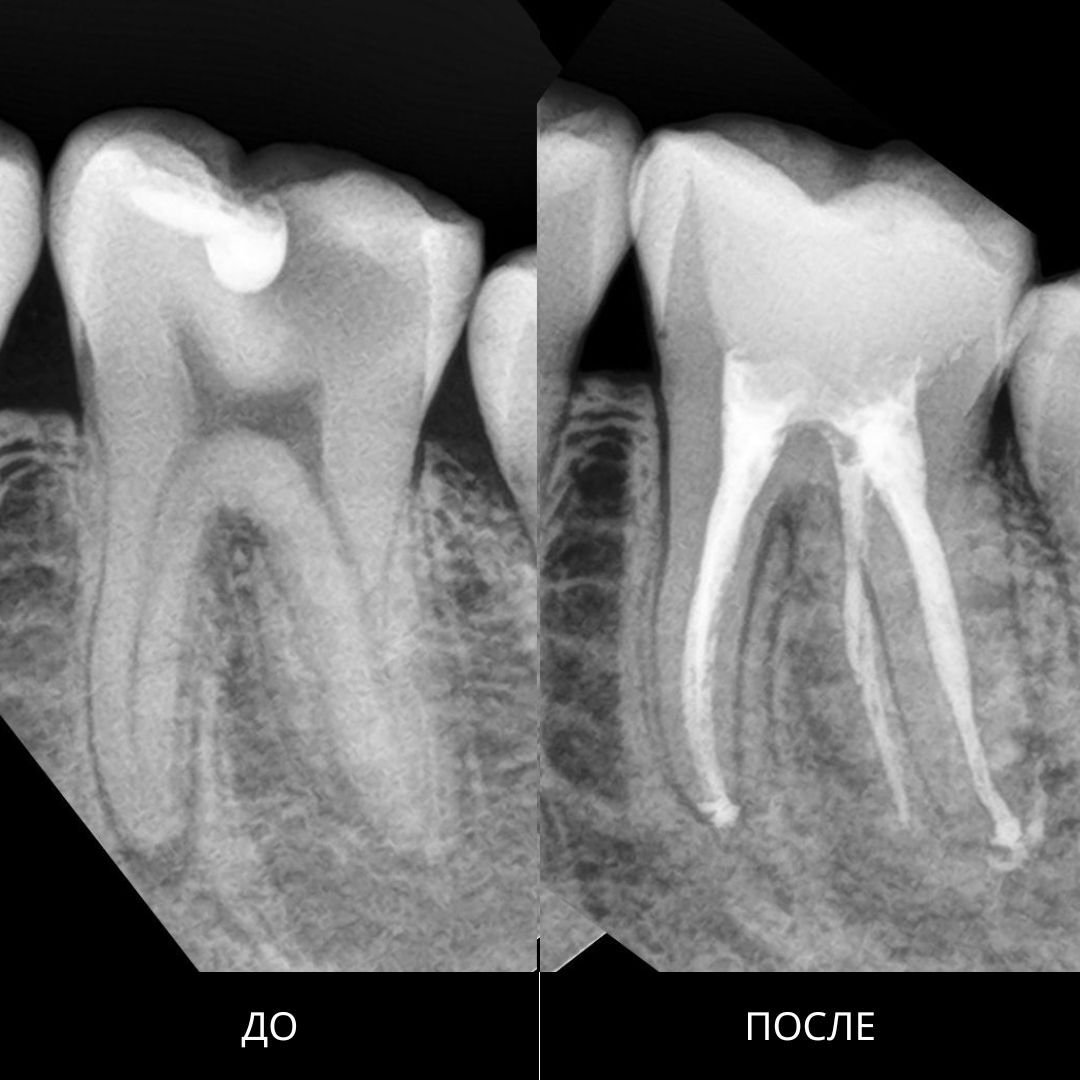

Провели тщательную чистку всех каналов, удалили инфицированные ткани и заполнили каналы лечебным материалом. Через 2 месяца наблюдений зуб полностью запломбировали и восстановили под коронку.